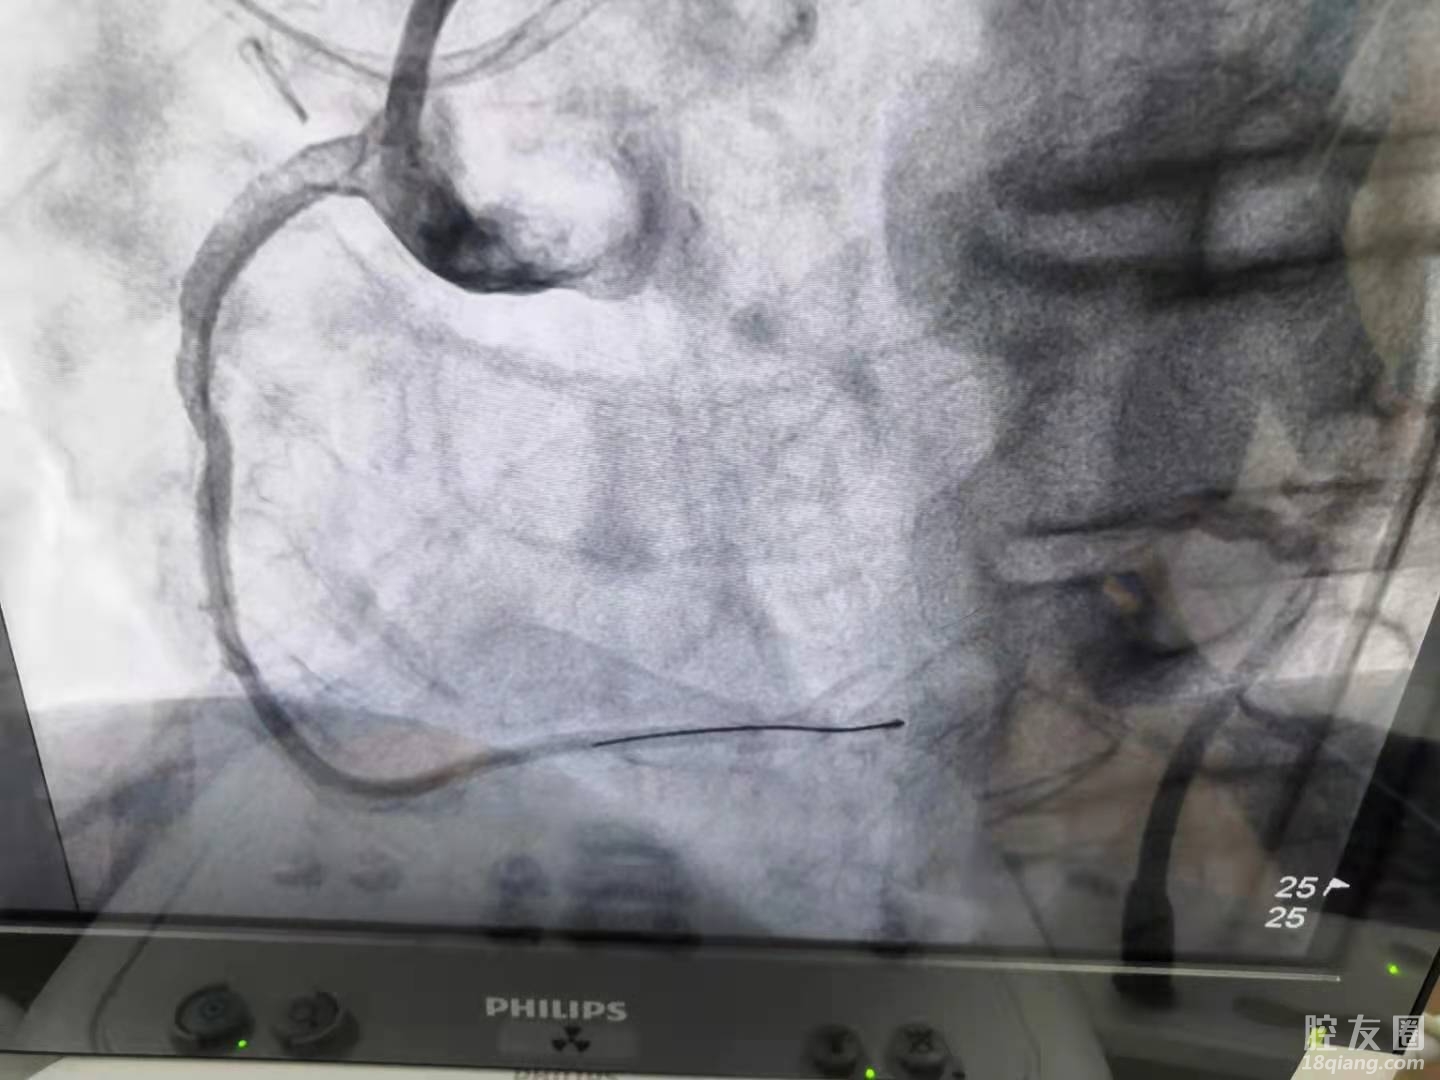

(术前)

术中,李主任对于闭塞的右冠状动脉,选择经右桡动脉,通过超强支撑导引导管7F AL1,左冠状动脉经股动脉也使用导引导管,对侧造影指引,反复尝试后,在微导管支撑下,第三根导丝成功通过病变。

一般情况下,导丝通过病变,手术很快就会结束,但该患者不一样,对于整场手术的艰苦战斗刚刚开始,因张先生右冠状动脉严重钙化,就像石头一样,器械难以通过,甚至造成微导管头端毁损,及球囊受损,难度很大。术中,李主任利用各种手术技巧,克服困难,前后一共使用了9个球囊,历经两个半小时,终于将病变顺利扩张,并在延长导管支持下,为患者成功植入两枚支架,顺利开通血管,完成手术。目前患者恢复良好,已顺利康复出院,后期定期复查即可。